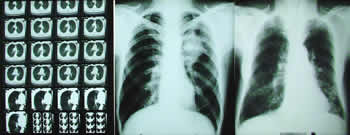

Snimci pluća |

Ispitivanje disajne funkcije – merenja i testovi - ima brojne svrhe, pre svega da pokaže kako pluća u celini rade, ali i da nas „dovede“ do tačnog mesta poremećaja. Dijagnostika plućnih bolesti počinje uobičajenim pregledom bolesnika. Može da obuhvati rendgenski snimak i endoskopiju; međutim, bez ispitivanja disajne funkcije, naglašava naš sagovornik, nema kompletne dijagnostike.

Postoji zabluda da se slušalicama može obaviti kompletan pregled pluća. Često nije dovoljno ni da se pregled dopuni snimkom pluća. Kod hronične opstruktivne bolesti, ovi pregledi mogu da pokažu normalne nalaze i pored toga što se bolesnici žale na teško disanje - tada samo spirometrija može da otkrije ili potvrdi da postoji suženje disajnih puteva. Ili, obrnuto, ponekad se pri slušanju posumnja na astmu, a spirometrija pokaže normalne nalaze, kada se verovatno radi samo o virusnoj infekcijii. Naš sagovornik ističe da je spirometrija apsolutno neophodna i za postavljanje dijagnoze i za razrešenje dijagnostičkih dilema; dakle onda kad, na primer, treba oceniti da li se sme seći deo pluća, ili da li je rizično uputiti pacijenta na operaciju srca, ili žučne kese koja se nalazi tik uz dijafragmu (za disanje vrlo bitan mišićni organ)...